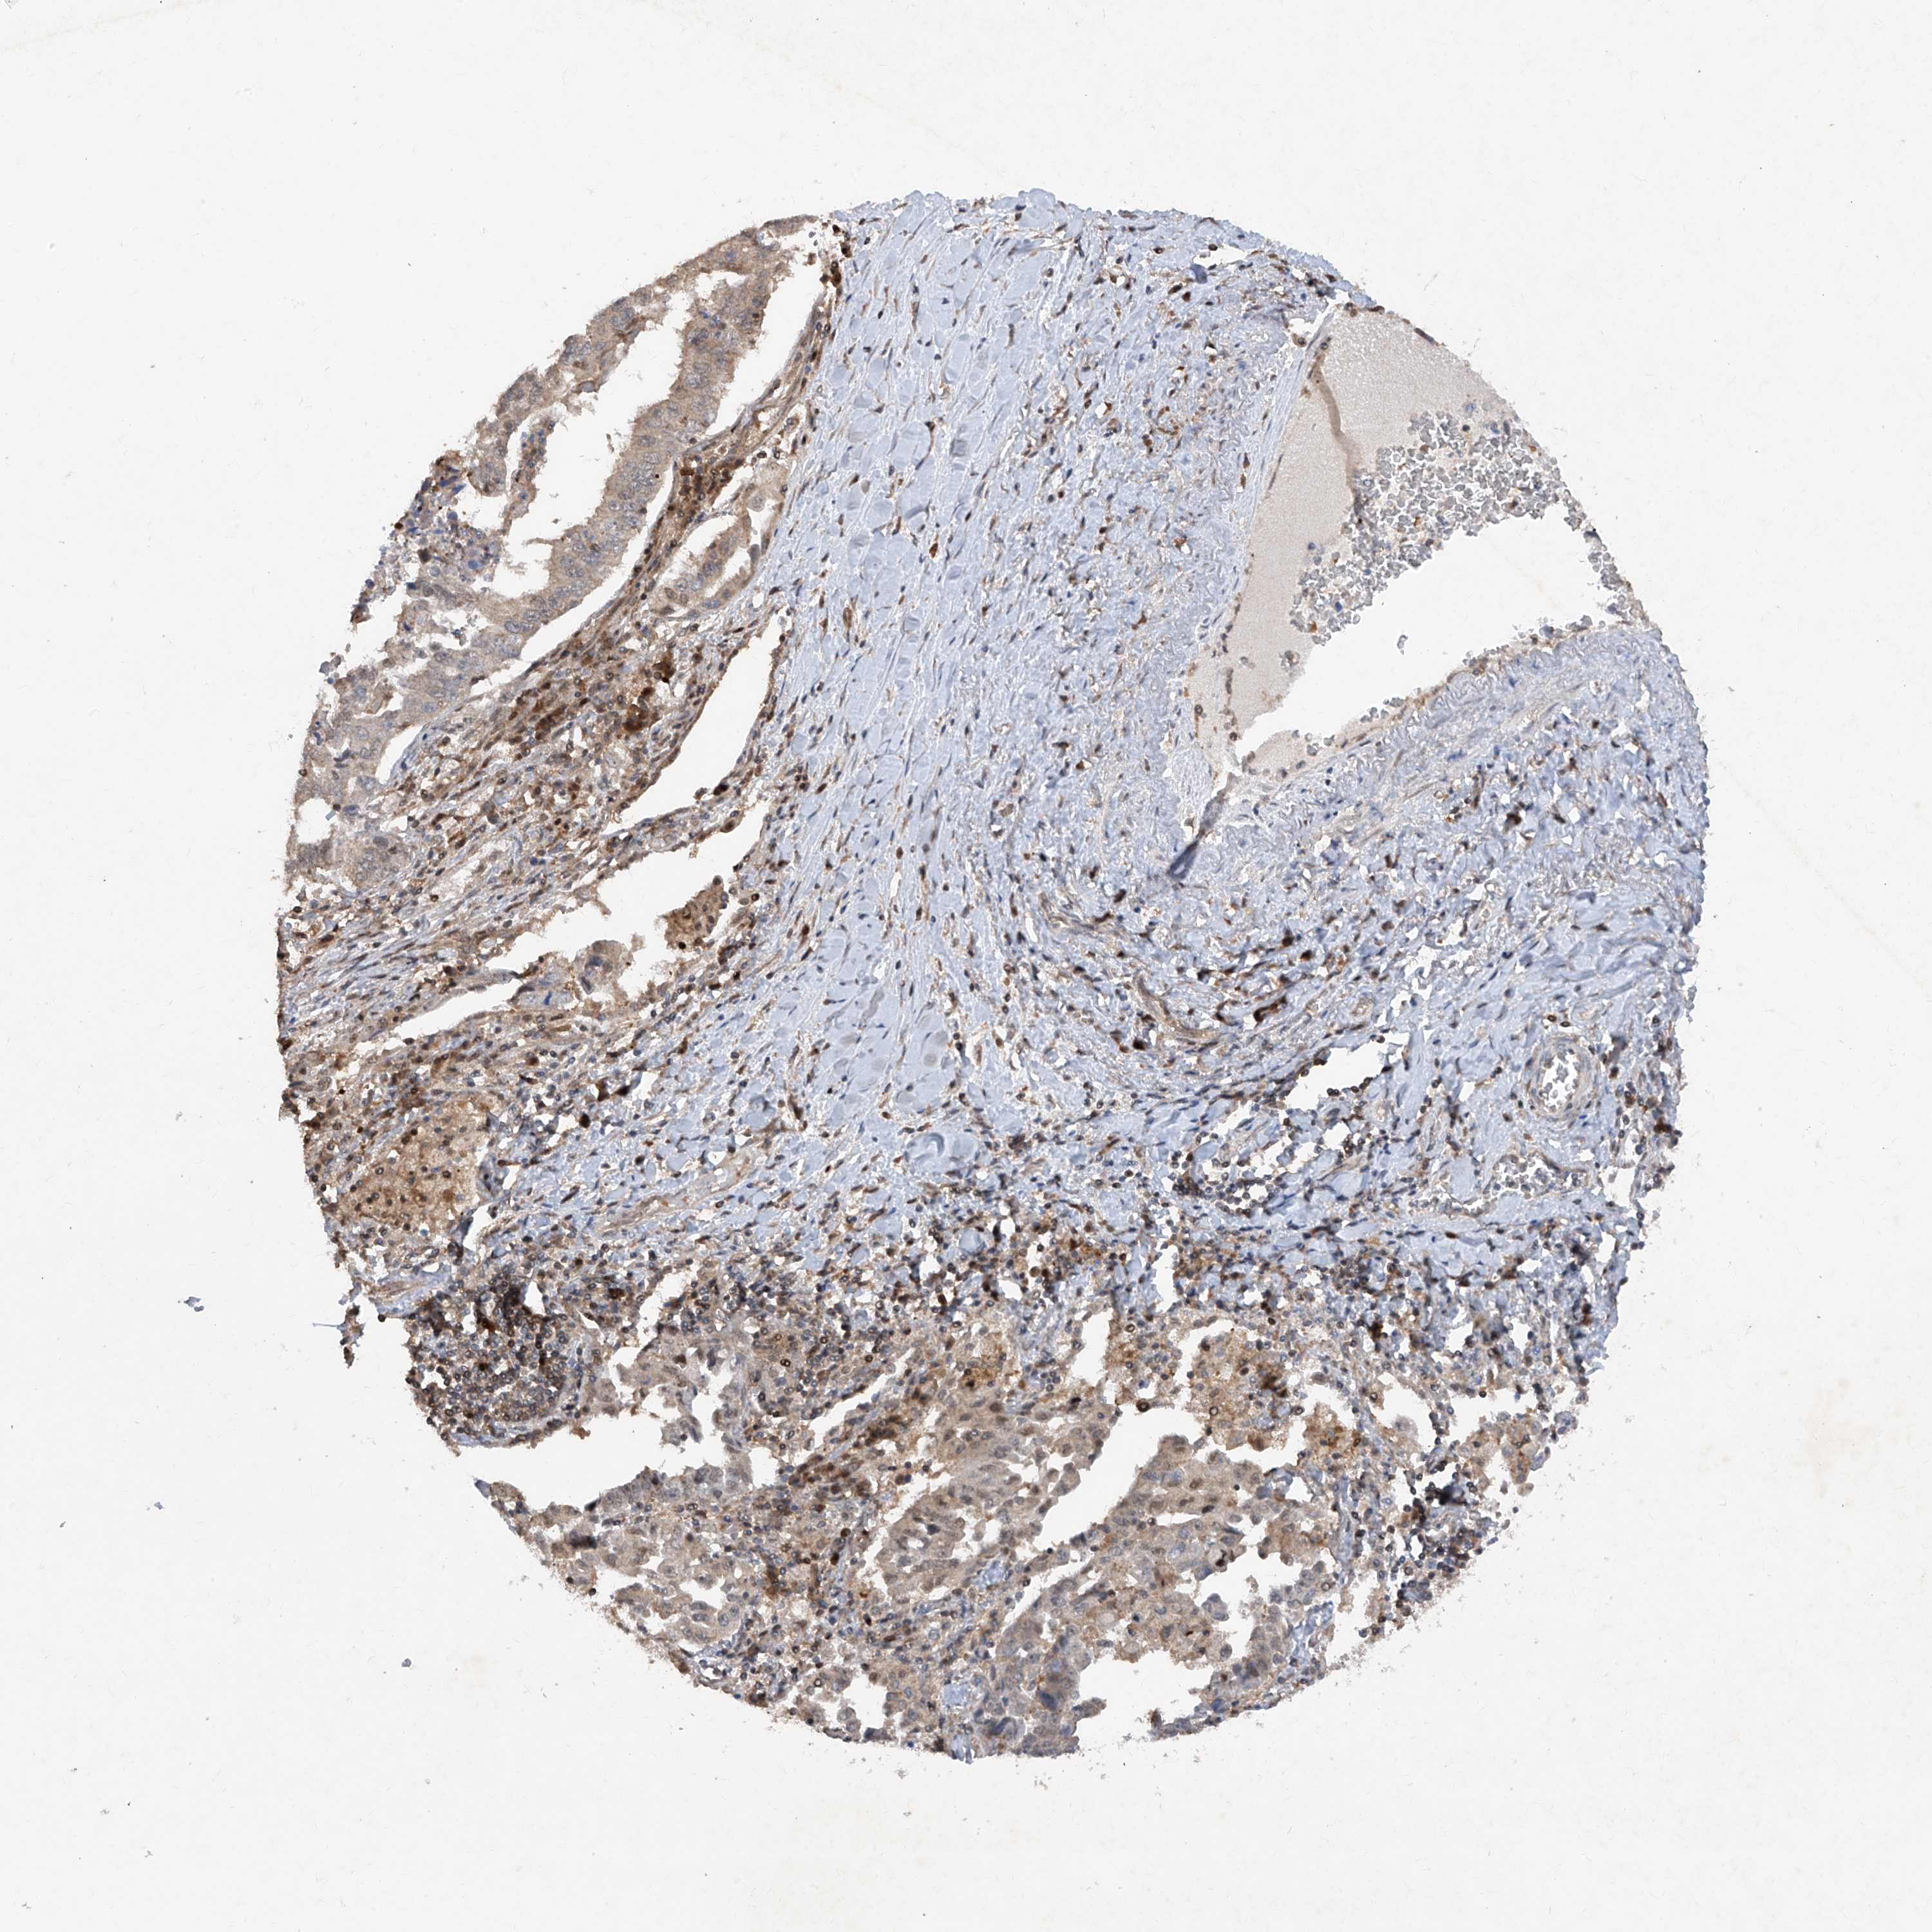

CANCER LUNG CANCER Show tissue menu

LUAD TCGA LUAD VALIDATION LUSC TCGA LUSC VALIDATION PROTEIN LUAD CPTAC PROTEIN LUSC CPTAC PROTEIN EXPRESSION

ANTIBODIES

AND

VALIDATION